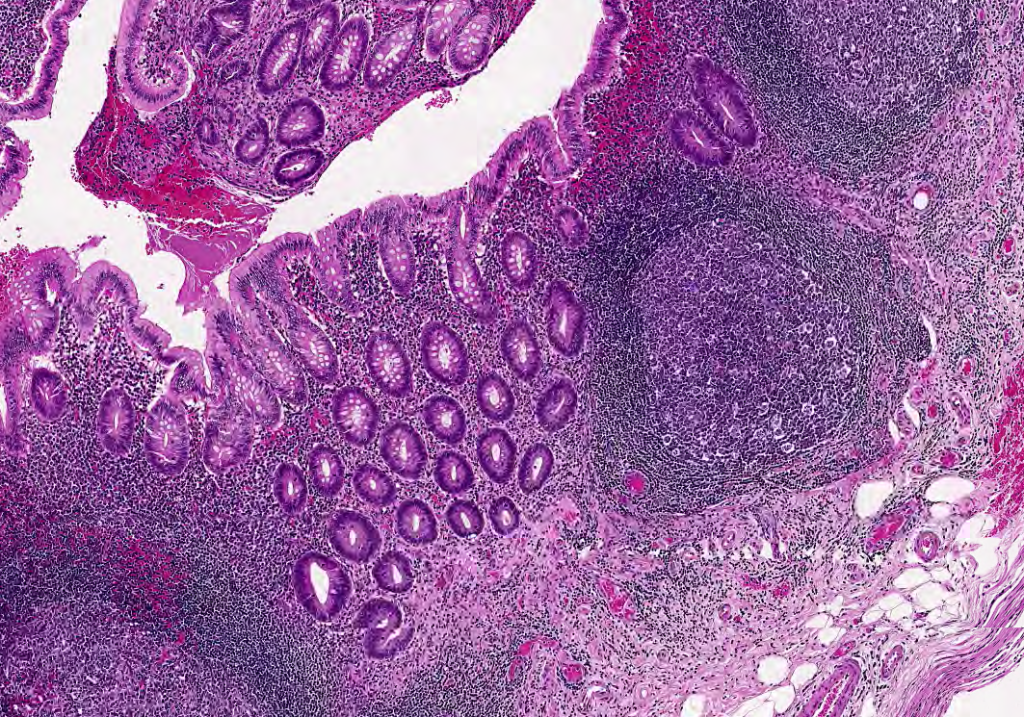

El bazo es un órgano encapsulado encargado de la eliminación de células senescentes, entre ellas los eritrocitos.Observe que el bazo carece de corteza y médula. Se organiza en pulpa blanca y pulpa roja.Se observa la cápsula de TCDi en contacto con la luz y la organización del bazo.Identifique las arteriolas centrales características de los nódulos linfáticos en el bazo.Arteriola central, Bazo, HyE.Las Vainas Linfáticas Periarteriolares (PALS) son cúmulos del Linfocitos T que rodean la arteriola central.La pulpa esplécnica nos permite identificar la organización del bazo, esta se divide en blanca y roja.Observe el nódulo linfático secundario, con su centro germinal, su zona del manto y una arteriola central.Bazo, HyE.Bazo, HyE.Bazo, Tinción de Giemsa.La arteriola central no siempre es «central», recuerda que puede ser desplazada por los linfocitos presentes en el nódulo linfático.Con impregnaciones argénticas podemos observar fibras reticulares (Colágena III)Delimitado con la línea negra podemos observar un nódulo linfoide secundario y señalado con la flecha negra observamos una arteriola central.Identifique.Identifique la arteriola central. Bazo, Tinción de Giemsa.Bazo de ratón, HyE.Identifique en la parte superior de la fotomicrografía la cápsula del bazo.